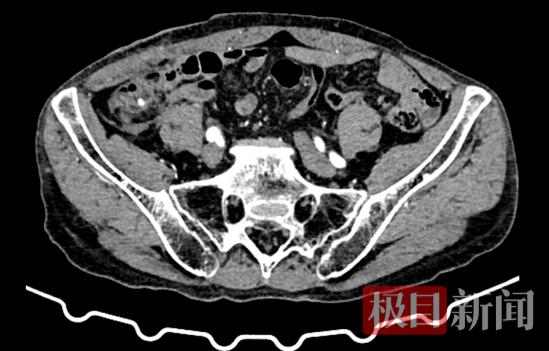

两周前,73岁的患者肖爹爹在外院行阑尾切除手术,术后病理诊断为阑尾恶性肿瘤,遂来到市一医寻求进一步治疗。

为确保治疗精准,医院结直肠癌多学科诊疗(MDT)团队迅速组织会诊,完善相关检查后,结合患者年龄、身体状况及肿瘤分期等情况进行综合研讨,最终确定采用前沿的“经脐单孔腹腔镜下右半结肠切除术”方案,力求在根治肿瘤的同时,最大程度减少手术创伤。